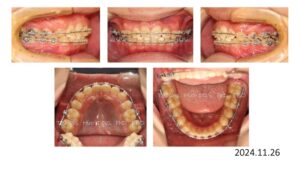

次は過蓋咬合です。

15歳の男の子、叢生と過蓋咬合で下顎前歯が見えないことを主訴に来院されました。

上顎両側4番を抜歯後、上顎にブラケットを付け、レベリング後、上顎前歯部の圧下を開始。

上顎前歯部の圧下が完了し、下顎にブラケットを付け、

2年7ヶ月間の動的治療をもって治療を終了しました。

上顎前歯の圧下量 4.5㎜、後退量 7.0㎜、治療前に Overbiteが深かったので、後戻りを考慮して浅く仕上げてあります。